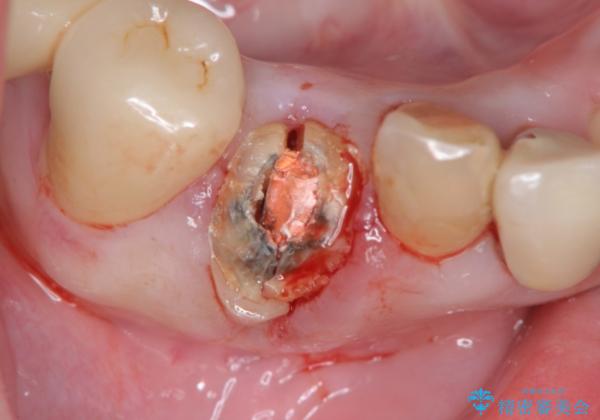

- 前歯の違和感、痛みの改善を希望され来院されました。

X線写真および歯周組織検査より、歯の破折 周囲骨の高度な吸収が認められました。

抜歯後、インプラントによる審美・機能改善を希望されたのでインプラント埋入に先立ち吸収した骨の再生を計画します。